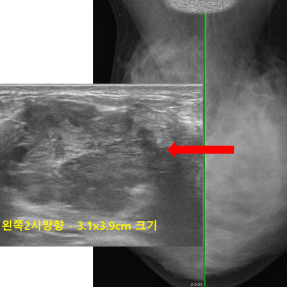

유방암 · 갑상선암 진단사례

Thyroid Clinic

정확한 검사와 해석으로 건강한 일상을 되돌려드립니다.